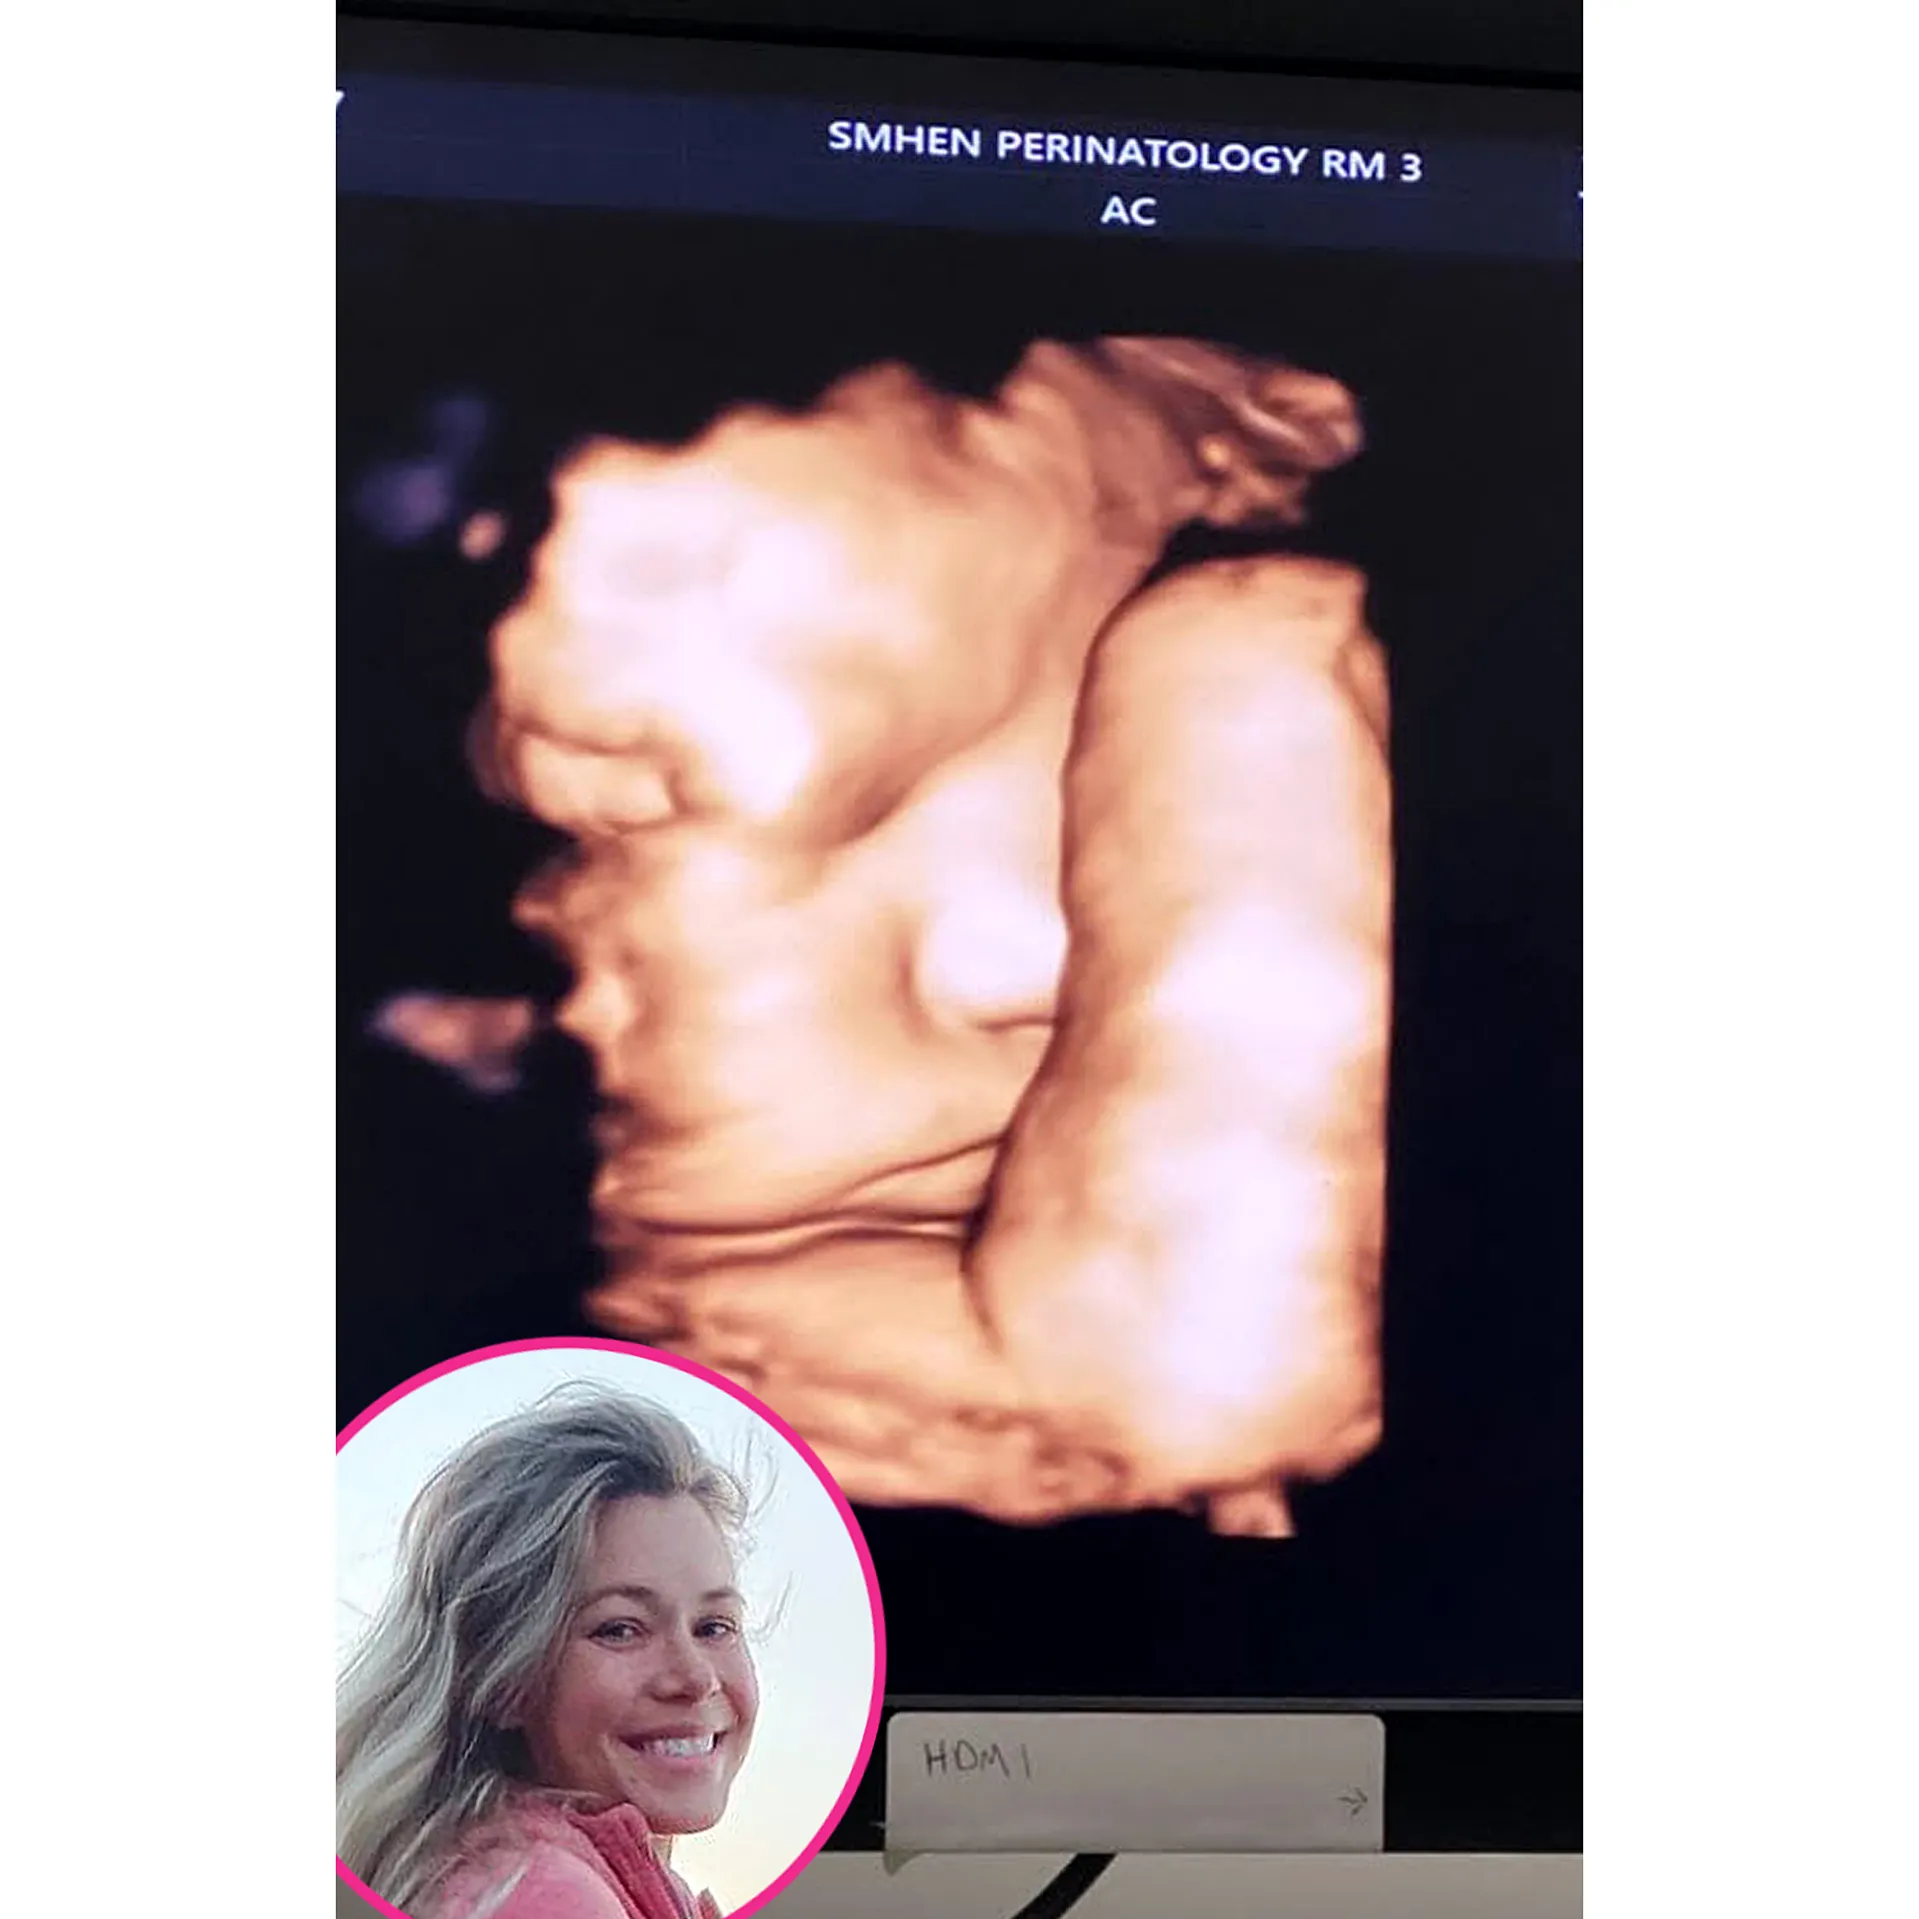

As for Perry, the Grammy nominee posted funny footage in May 2020 from her and Orlando Bloom’s appointment ahead of their daughter’s birth.

“When your unborn daughter gives you a middle finger from the womb you know you’re in for it. #happymothersdaytome,” the “I Kissed a Girl” singer captioned a social media upload at the time. The baby-to-be shifted in the footage and stuck up one of her fingers.